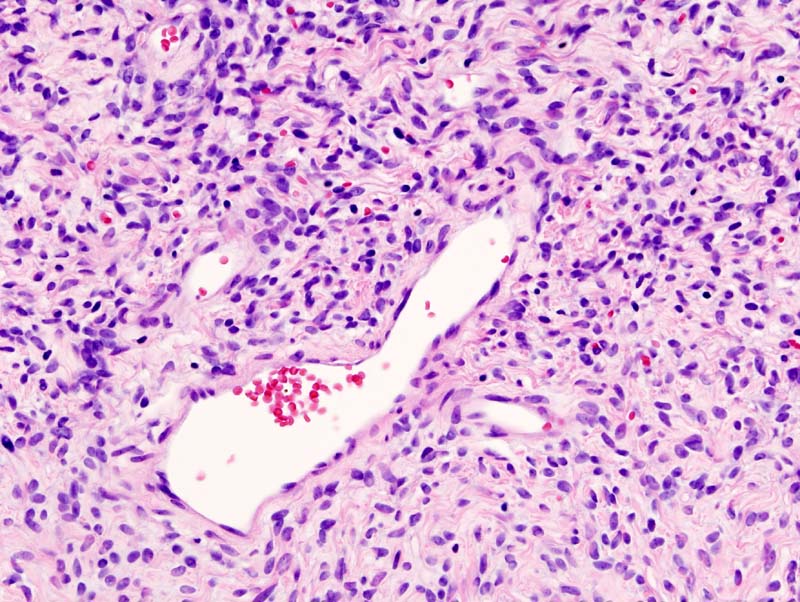

Solitary Fibrous Tumors(SFT) | Canada | PDF | PPT| Case Reports

www.omicsonline.org

www.omicsonline.org fibrous solitary tumors sft tumor pdf disease pleura malignant rare symptoms ppt articles